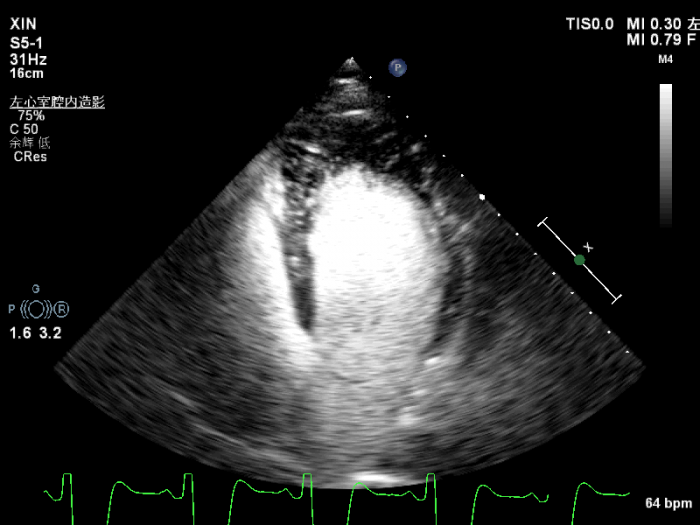

经左心声学造影提示,心尖四腔心:心尖部心肌明显肥厚,呈”黑桃样”改变,心尖部心肌灌注稀少。